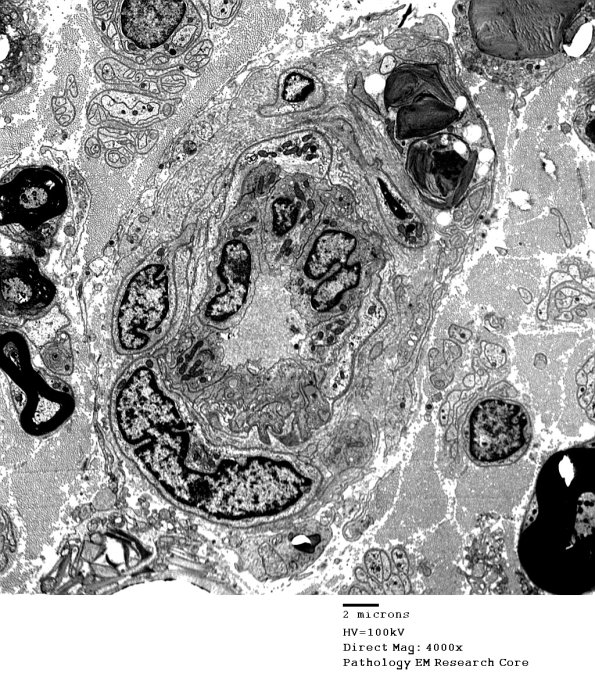

Washington University Experience | PERIPHERAL NEUROPATHY | 4 AXONAL DEGENERATION | 4 Macrophages | 4I1 Axonal Degeneration (Case 4) 021 - Copy

4I1 Axonal Degeneration (Case 4) 021 - Copy

Macrophages may leave the endoneurium with partially digested material.